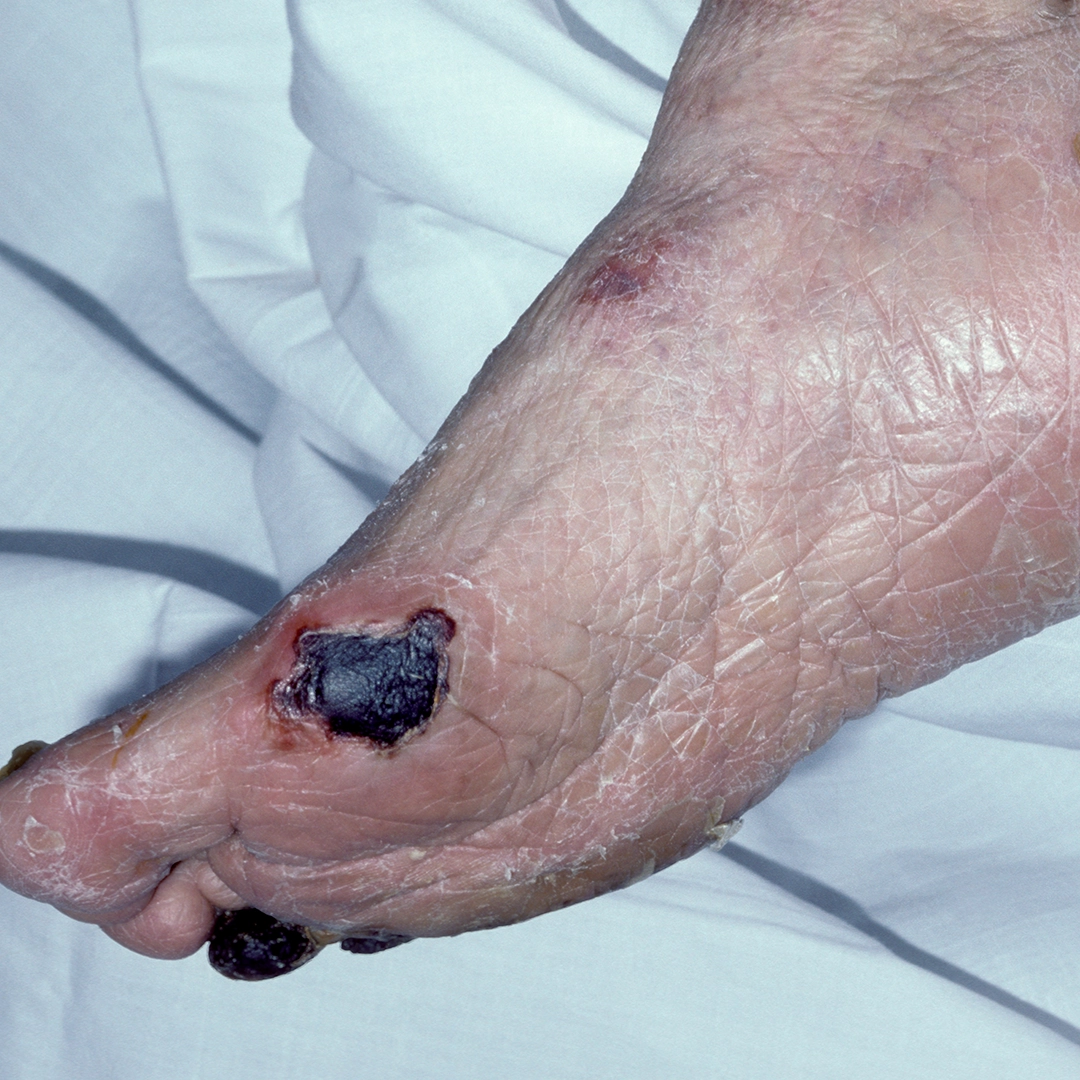

It is currently unknown if Chinese people with type 2 diabetes mellitus (T2DM) who exhibit the hypertriglyceridemic-waist (HTGW) phenotype have a higher risk of developing diabetic foot ulcers (DFU). 2651 consecutive individuals suffering from T2DM (mean age 56±11 years, 58% female) with a mean T2DM duration of 9.3 years showed the connection. According to the IDF criteria for metabolic syndrome, HTGW was diagnosed if TG was more than or equal to 1.70 mmol/L and a waist circumference of more than or equal to 80 cm for women and more than or equal to 90 cm for men. The research population was then divided into two subgroups: HTGW and Non-HTGW. The IWGDF 2019 recommendations for the diagnosis and management of foot infections in people with T2DM were followed in the diagnosis of DFU. A logistic regression analysis was used to link the DFU and HTGW phenotype. Patients with and without HTGW had corresponding prevalences of DFU of 9.3% and 4.2%. The systolic blood pressure was greater in the HTGW phenotypic group (139.2 mmHg vs. 132.7 mmHg, p<0.05), fasting plasma glucose (9.1 mmol/L vs. 8.5 mmol/L, p<0.05), HbA1c [73 mmol/mol (8.83%) vs. 63 mmol/mol (7.95%), p<0.05], apolipoprotein B (0.95 g/L vs. 0.89 g/L, p<0.05), C-reactive protein (8.23 mg/L vs. 4.92 mg/L, p<0.05), and TNF-α ( 26.46 pg/ml vs. 16.80 pg/ml, p<0.05) but lower levels of apolipoprotein A1 (1.21g/L vs. 1.33g/L, p<0.05). Upon consideration of factors such as age, sex, body mass index, length of T2DM, smoking, HbA1c, apolipoprotein B, and C-reactive protein, the hypertriglyceridemic-waist phenotype was linked to DFU (OR 1.33, 95% CI 1.03-2.71). Simultaneous testing of triglycerides and waist circumference in patients with T2DM may be a cheap and easy way to find those who are more likely to develop DFU.